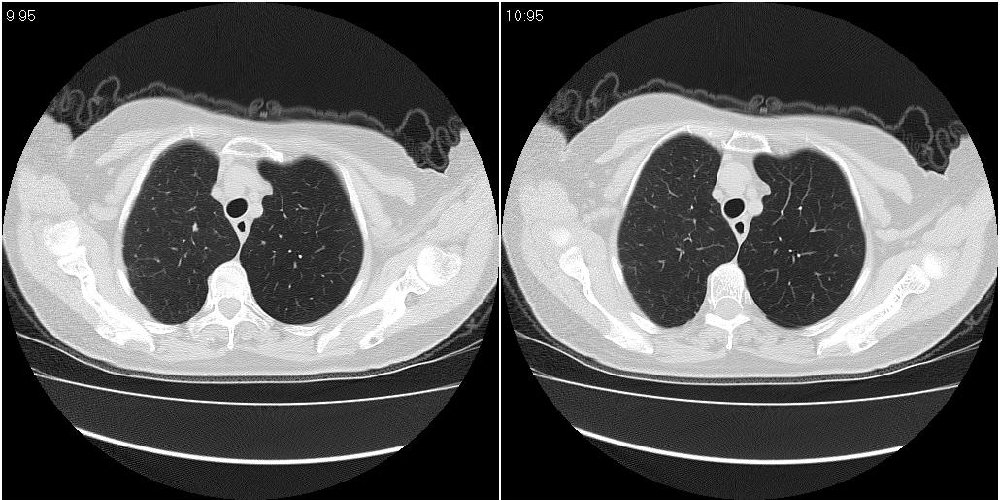

女性,72岁。去年9月份发现肺部病变,诊为肺结核并进行正规治疗至今,但复查后发现ct表现几乎没有变化。

右侧中叶支气管明显狭窄,建议行纤支镜检查!

右中间段支气管局限性狭窄,右中叶支气管亦稍显狭窄,但并未见明显占位表现,半年多了,无变化也许是好事,可能为炎性狭窄,建议继续随访。

双肺继发型tb并右中叶内膜tb,轻度支扩,左下胸膜肥厚粘连。

右中叶炎性改变,支气管狭窄但较光滑,占位可能性不大。

右中间段支气管局限性狭窄,右中叶支气管亦稍显狭窄.